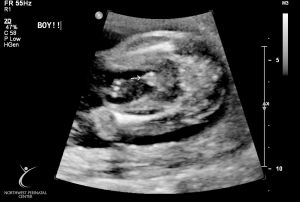

Last Ultrasound